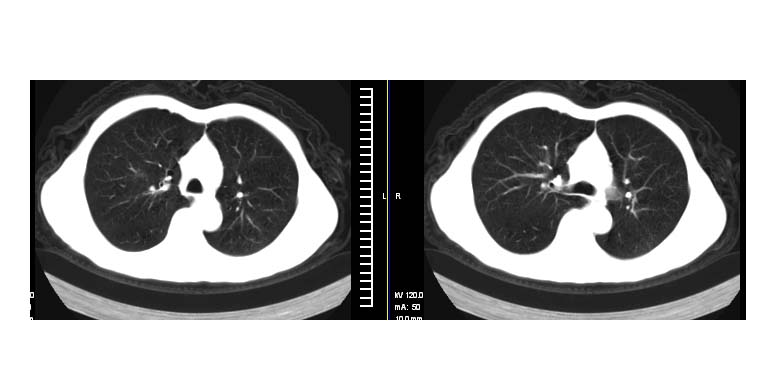

标题: CT11019:男性,66岁。发烧5-6天。治疗后无明显好转。 [打印本页]

标题: CT11019:男性,66岁。发烧5-6天。治疗后无明显好转。

左下肺中央型肺癌伴阻塞性肺炎\\肺不张可能性大,建议支纤镜检查.

左下肺中心性肺癌伴下肺不张及周围阻塞性炎症

左下肺中央型肺癌伴阻塞性肺炎\\肺不张可能性大,建议支纤镜检查

左下肺中心性肺癌伴下肺不张及周围阻塞性炎症,

建议:支气管镜检查。

左肺门下分增大见有结节影,基底干及分支显示不清,下叶体积缩小,呈片带状机磨玻璃样影显示。支持考虑左下肺中心型肺癌伴阻塞性肺炎及部分肺不张。建议纤支镜检查